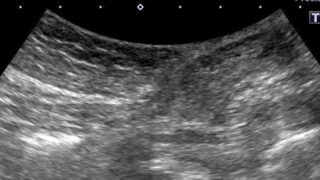

症例 腹壁瘢痕ヘルニアのエコー所見と鑑別|見逃しやすいポイントと症例で解説【試験対策】 腹壁瘢痕ヘルニアの超音波検査で押さえるべき所見、術後症例の特徴、鑑別の考え方をまとめました。最新の急性腹症診療ガイドライン2025(第2版)の内容も踏まえて解説しています。超音波検査士受験者・新人技師の学習に最適です。 2025.12.01 症例